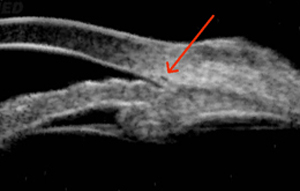

?сследование при помощи VuMAX® функций проходимости в случаях трабекулэктомии и конъюнктивальном химозе, можно оценить успешность и эффективность проведенных пост-оперативных вмешательств таких, как фильтрующая хирургия. Кроме того, VuMAX® обеспечивает четкую визуализацию Шлеммова канала, что необходимо в случаях проведения вискоканалостомии.